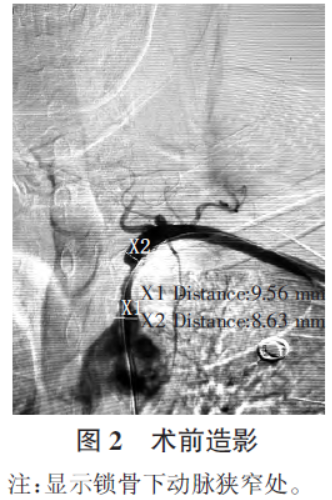

头颈部CT 血管造影检查(图1)显示,左侧锁骨下动脉起始部附壁血栓,管腔中度狭窄。入院后第2 天在局部浸润麻醉下行经股动脉插管全脑血管造影术发现,左侧锁骨下动脉起始部重度狭窄,狭窄近端正常血管直径X1=9.56mm,狭窄远端正常血管直径X2=8.63 mm,最狭窄处直径X3=2.3 mm,根据椎动脉支架试验(vertebral artery stenting trial, VAST)程度计算公式[(X1+X2)/2-X3]/(X1+X2)×100%得到狭窄程度为37.4%,见图2。